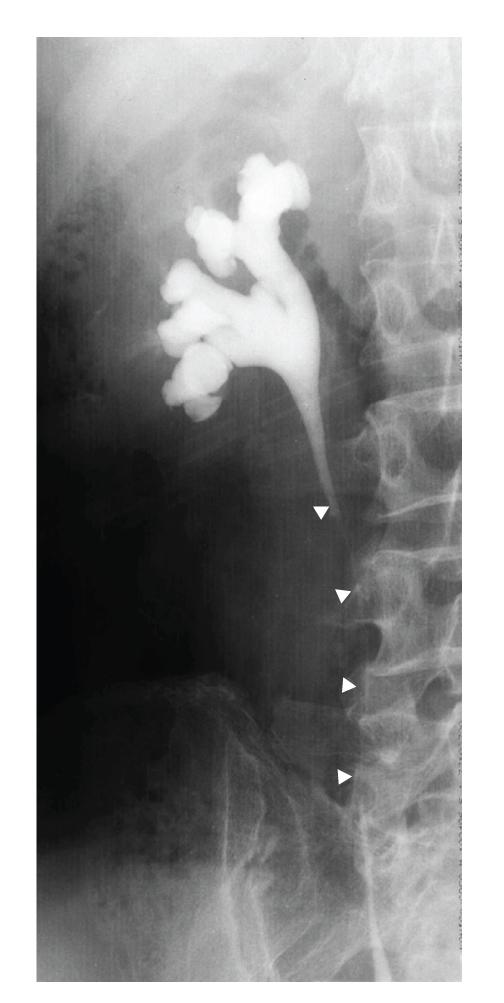

Metastases from a variety of malignant tumors can involve the ureters, but ureteral involvement by lung cancer is extremely rare and usually described at autopsy. We report a rare case of a 76-year-old man who presented with a three-month history of right flank dullness and was noted to have a nonhomogeneous retroperitoneal mass with hydronephrosis of the right kidney on computed tomography of the abdomen. Computed tomography of the thorax showed a nodule in the lower lobe, measuring 3 × 2 cm, in the right lung. After excluding the presence of other primary tumors and metastases, we reached a final diagnosis of solitary retroperitoneal metastasis of adenocarcinoma of the lung. Although rare, in patients of non-small cell lung cancer, presence of hydronephrosis should alert the physician to the possibility of metastasis.

摘要

多种恶性肿瘤的转移灶可累及输尿管,但肺癌累及输尿管极为罕见,通常在尸检时才被描述。我们报告一例罕见病例,一名76岁男性,有三个月的右侧腰部钝痛病史,腹部计算机断层扫描显示有一个不均匀的腹膜后肿块,右肾积水。胸部计算机断层扫描显示右肺下叶有一个3×2厘米的结节。在排除其他原发性肿瘤和转移灶后,我们最终诊断为肺腺癌孤立性腹膜后转移。虽然罕见,但在非小细胞肺癌患者中,出现肾积水应提醒医生注意转移的可能性。